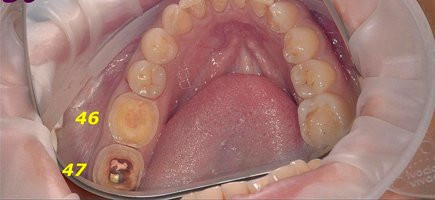

Установка керамической коронки

Специалисты клиники «Доктор Дент» провели реставрацию зубов 3/4 коронками на аппарате CEREC за одно посещение!!! 47 зуб отреставрирован цифровой цельнокерамической коронкой Empress, а 46 зуб — упроченной цифровой цельнокерамической

Доктор: Смирнова Людмила Игоревна